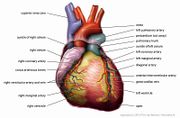

| 30. 4. 2011, 07:40 | Anatomie srdce.jpg (soubor) |  | 91 kB | Webmaster | (Zdroj: http://en.wikipedia.org/wiki/File:Anatomy_Heart_English_Tiesworks.jpg) | 1 |